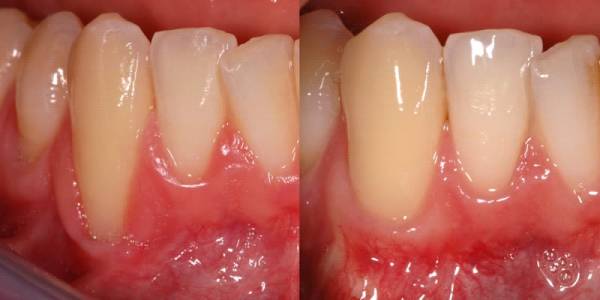

⦁ لثه هایتان درحال عقب روی است:

آیا به تازگی متوجه شده اید که طول دندانهایتان زیاد شده و یا لثه هایتان در حال عقب روی ست؟ این علایم نشانه ی بیماری لثه می باشد که حتما باید برای کنترل آن به متخصص لثه مراجعه کنید.

ممکن است درد حاصل شده، ناشی از دندانهایی باشد که بلندتر به نظر می رسند بنابراین زمانی که مسواک می زنید حواستان به چرک، زخم های دهانی، تنفس بدبو و خونریزی باشد.